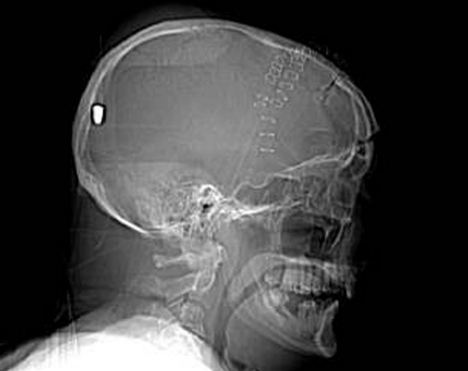

CT掃描顯示子彈留在彼得老人的腦部

據(jù)英國《每日郵報》5月11日報道,英國一名61歲的老人上個月19日在花園干活時被一顆流彈擊中腦部竟奇跡存活,目前他半身癱瘓但無生命危險。5月10日,警方為了破案公布了彼得先生的腦部掃描圖片,希望知情者提供相關(guān)線索。

事情的經(jīng)過是這樣的,彼得在整理花園的時候突然摔倒在地不省人事,他的家人還以為他中風(fēng)了,但醫(yī)院對其大腦掃描后卻發(fā)現(xiàn)了令人驚悚的事實(shí):一顆子彈不知由于何種原因從左眼窩進(jìn)入他的大腦,并深深植入其腦后部。但不可思議的是彼得竟然活了下來,雖然身體部分癱瘓且失去了語言和記憶能力。

負(fù)責(zé)調(diào)查此案的警官史蒂夫表示:“這可能是我調(diào)查過的最詭異的一個案子了。”經(jīng)過對掃描圖片的鑒定,警方彈道專家賈爾斯認(rèn)為這顆子彈很像是從一種通常用于射殺兔子的.22口徑獵槍里射出的。

“如果在10碼外開這種槍,子彈會穿透彼得的腦部,但若是從800到1000碼以外,子彈會失去大部分的沖擊力,只能穿透軟組織。所以說,在這個距離內(nèi),子彈若射中彼得腦殼會被彈回,不可能進(jìn)入腦中,”賈爾斯說。